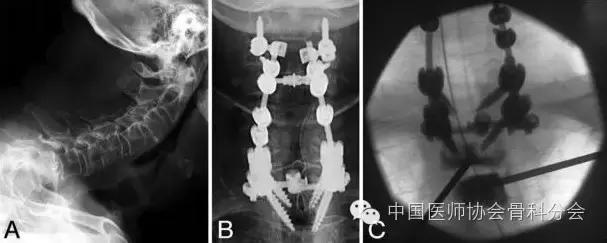

图4. 病例2.A:术前颈椎和上胸椎的侧位片显示颈椎严重的鹅颈畸形和前方的半脱位。B:术后正位片显示后路颈2-胸2钉棒固定和融合。C:术中X线片显示经椎间盘穿刺进入胸2椎体和经椎弓根穿刺进入胸3椎体,并且已经注入骨水泥